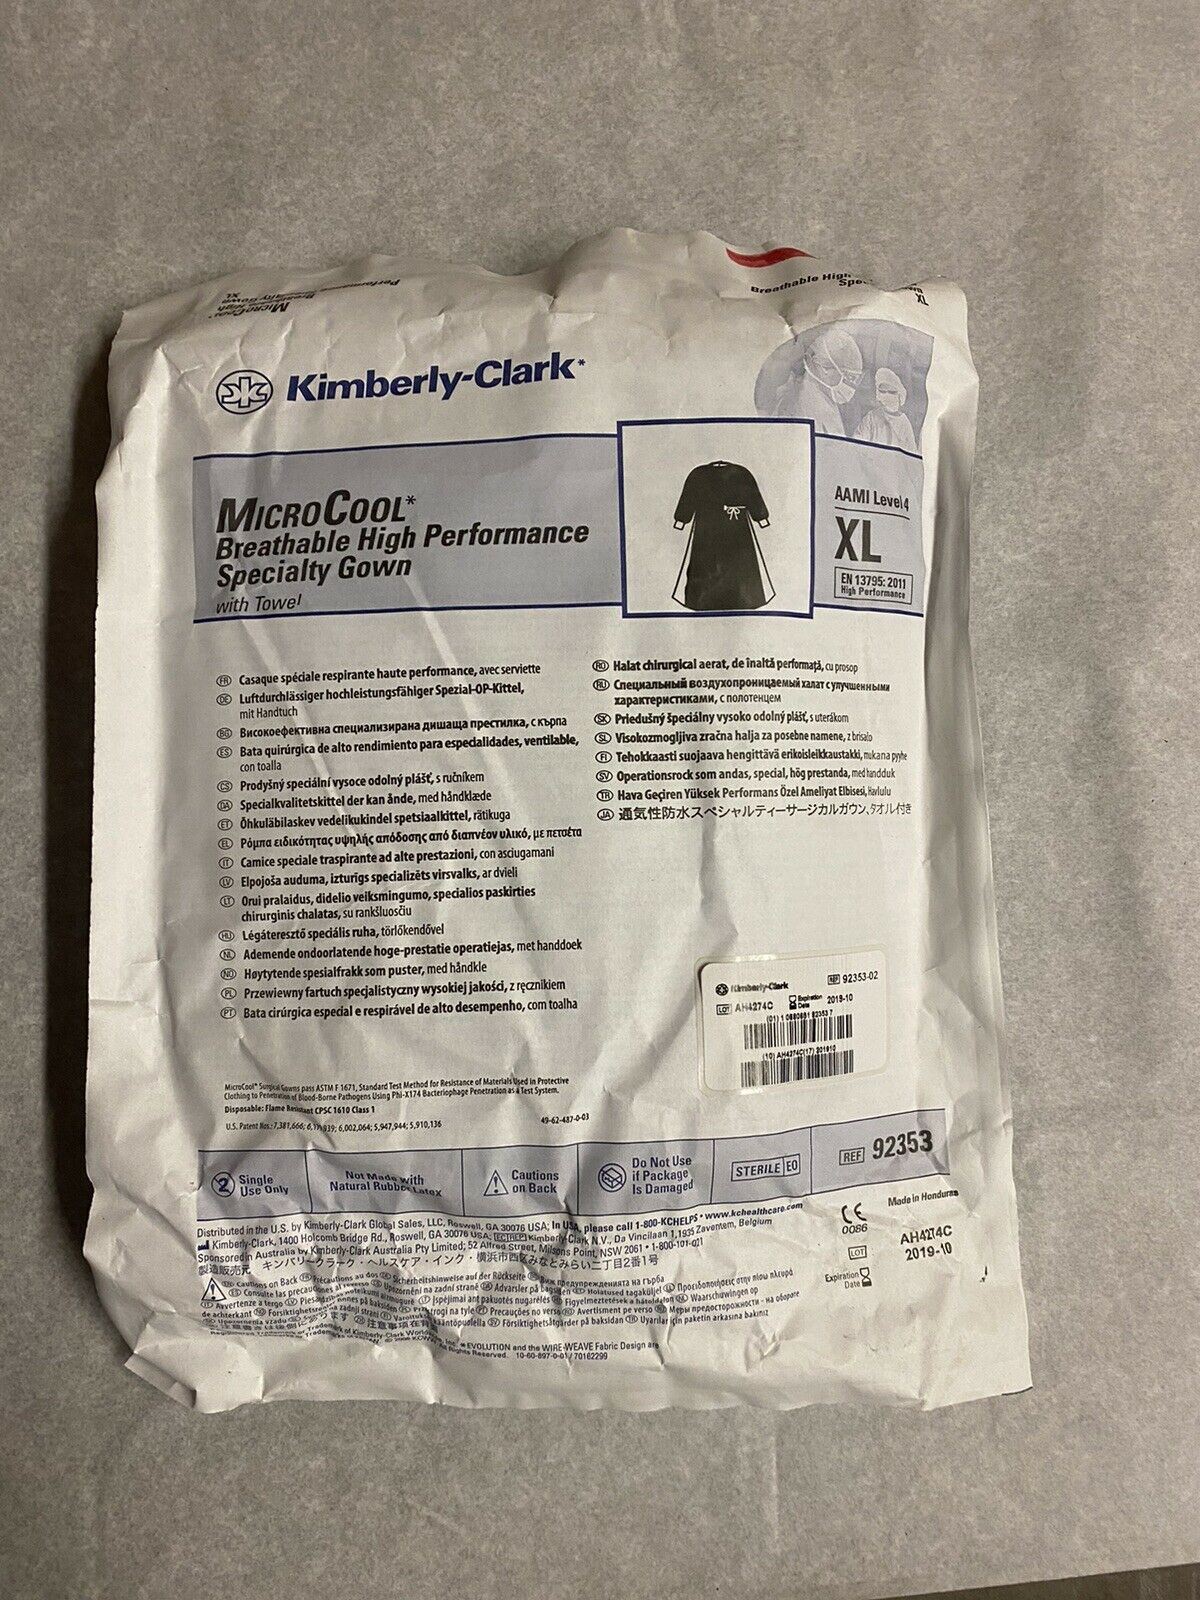

Save $ 2.52

DIAGNOSTIC ULTRASOUND MACHINES FOR SALE

Kimberly Clark MicroCool High Performance Surgical Gown Large 92353 AAMI 4 XL

Sale price$ 11.47

Regular price$ 13.99